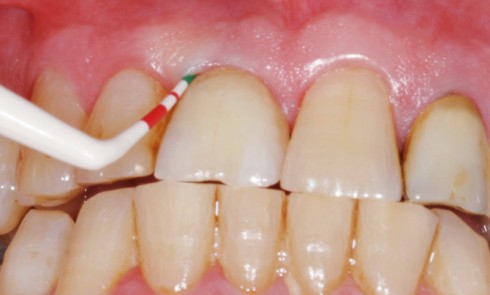

Article réservé à nos abonnés Le rôle de l’omnipraticien dans la maintenance implantaire

Si les complications et la perte des implants peuvent être dues à une surcharge occlusale, associée ou non à un...